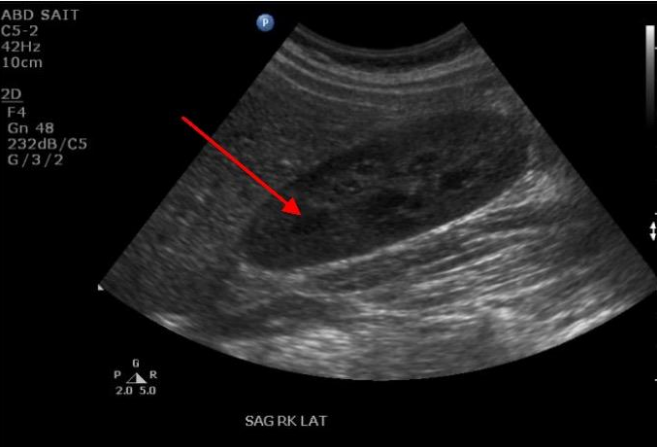

7

Q

Label the Red and blue arrows

A

Red: Right quadratus laborum

Blue: Right kidney pyramid of the medulla